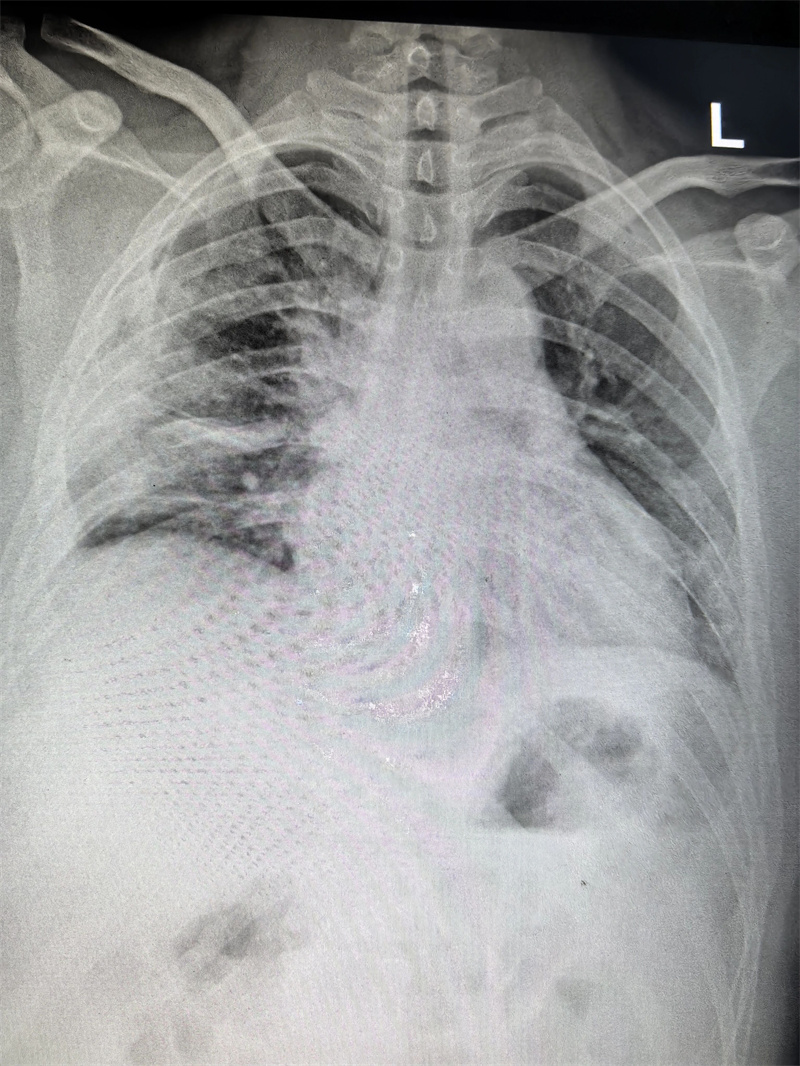

四个月前,23岁的小雨(化名)因胸闷前往医院就诊,CT检查结果显示右侧胸腔靠上位置出现包裹性脓胸,并进行穿刺检查,最终确诊为结核性包裹性脓胸,这个消息让小雨和家人陷入了深深的焦虑之中。

看着日益憔悴的小雨,医生建议手术治疗。术前,田子刚主任和宋巍峰医生在全面评估了小雨各项指标后,确定符合手术标准,便与麻醉科以及护理团队紧密配合,为小雨实施胸腔镜下胸膜剥脱术。

经过3个小时的紧张操作,包裹的脓肿被完整剥除,病灶彻底清除。术后切开脓肿,其内可见脓液,干酪物和坏死肉芽组织。

小雨的手术切口很小,大约只有4厘米,出血量也仅100ml,这对小雨的愈后起到了很好的作用。术后,小雨在医护人员的精心照料下恢复得很快,于10月24日顺利出院。